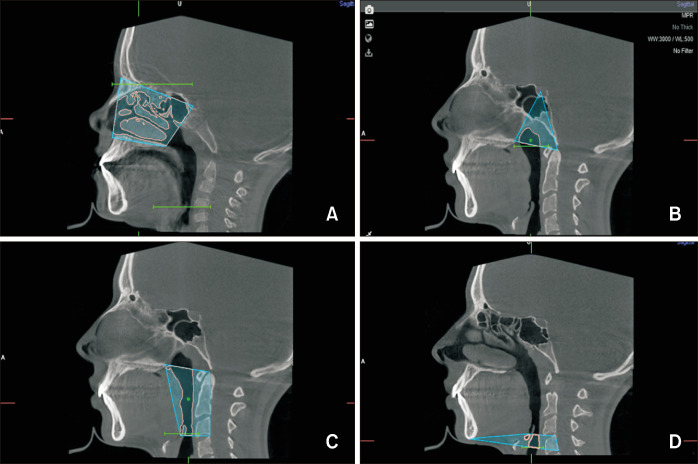

目的方法:使用 NemoFab Ortho 软件分析随机选取的 106 名正畸患者的锥形束计算机断层扫描图像:方法:使用 NemoFab Ortho 软件分析了随机抽取的 106 名正畸患者的锥形束计算机断层扫描图像。评估的牙齿骨骼变量包括面部前高(AFH)、面部后高(PFH)、PFH/AFH 比值、舌骨位置、上颌宽度(MW)和腭深。我们还使用相同的软件评估了 UA 体积(按解剖区域和整体进行评估)。我们还评估了不同年龄组和性别组之间 UA 变量的潜在差异。我们使用皮尔逊相关系数(R)计算了牙骨质参数和 UA 体积之间的相关性。方差分析和学生 t 检验用于评估不同年龄和性别间 UA 变量的差异。统计分析使用 SPSS 软件(Windows 版本 26)进行:该研究发现,PFH、AFH 和 MW 是与 UA 体积最密切相关的牙骨质参数。然而,ANB 角与 UA 体积没有明显的相关性。此外,不同年龄组的 UA 体积也存在差异。在 "8-12 "和"≥16 "年龄组中,口咽和咽部体积均存在性别差异:总之,我们的研究结果表明,UA体积与牙齿骨骼参数之间存在显著相关性,尤其是与面部高度和MW相关的参数。

Methods: Cone-beam computed tomography images of 106 randomly selected orthodontic patients were analyzed using NemoFab Ortho software. The dentoskeletal variables assessed were anterior facial height (AFH), posterior facial height (PFH), PFH/AFH ratio, hyoid position, maxillary width (MW), and palatal depth. The UA volume (evaluation in anatomical regions and as a whole) was also assessed using the same software. We also evaluated potential differences in UA variables between age and sex groups. The correlation between the dentoskeletal parameters and UA volume was calculated using the Pearson correlation coefficient (R). Analysis of variance and Student's t test were performed to assess differences between age and sex for UA variables. Statistical analyses were performed using SPSS software (version 26 for Windows).